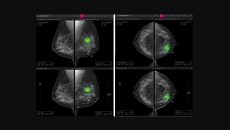

mammography

Australian researchers look at the possibility of integrating cardiovascular risk screening with routine breast screening by using AI and mammograms.

The company has developed a line of products targeting the mammography space to enable early and accurate breast cancer detection.